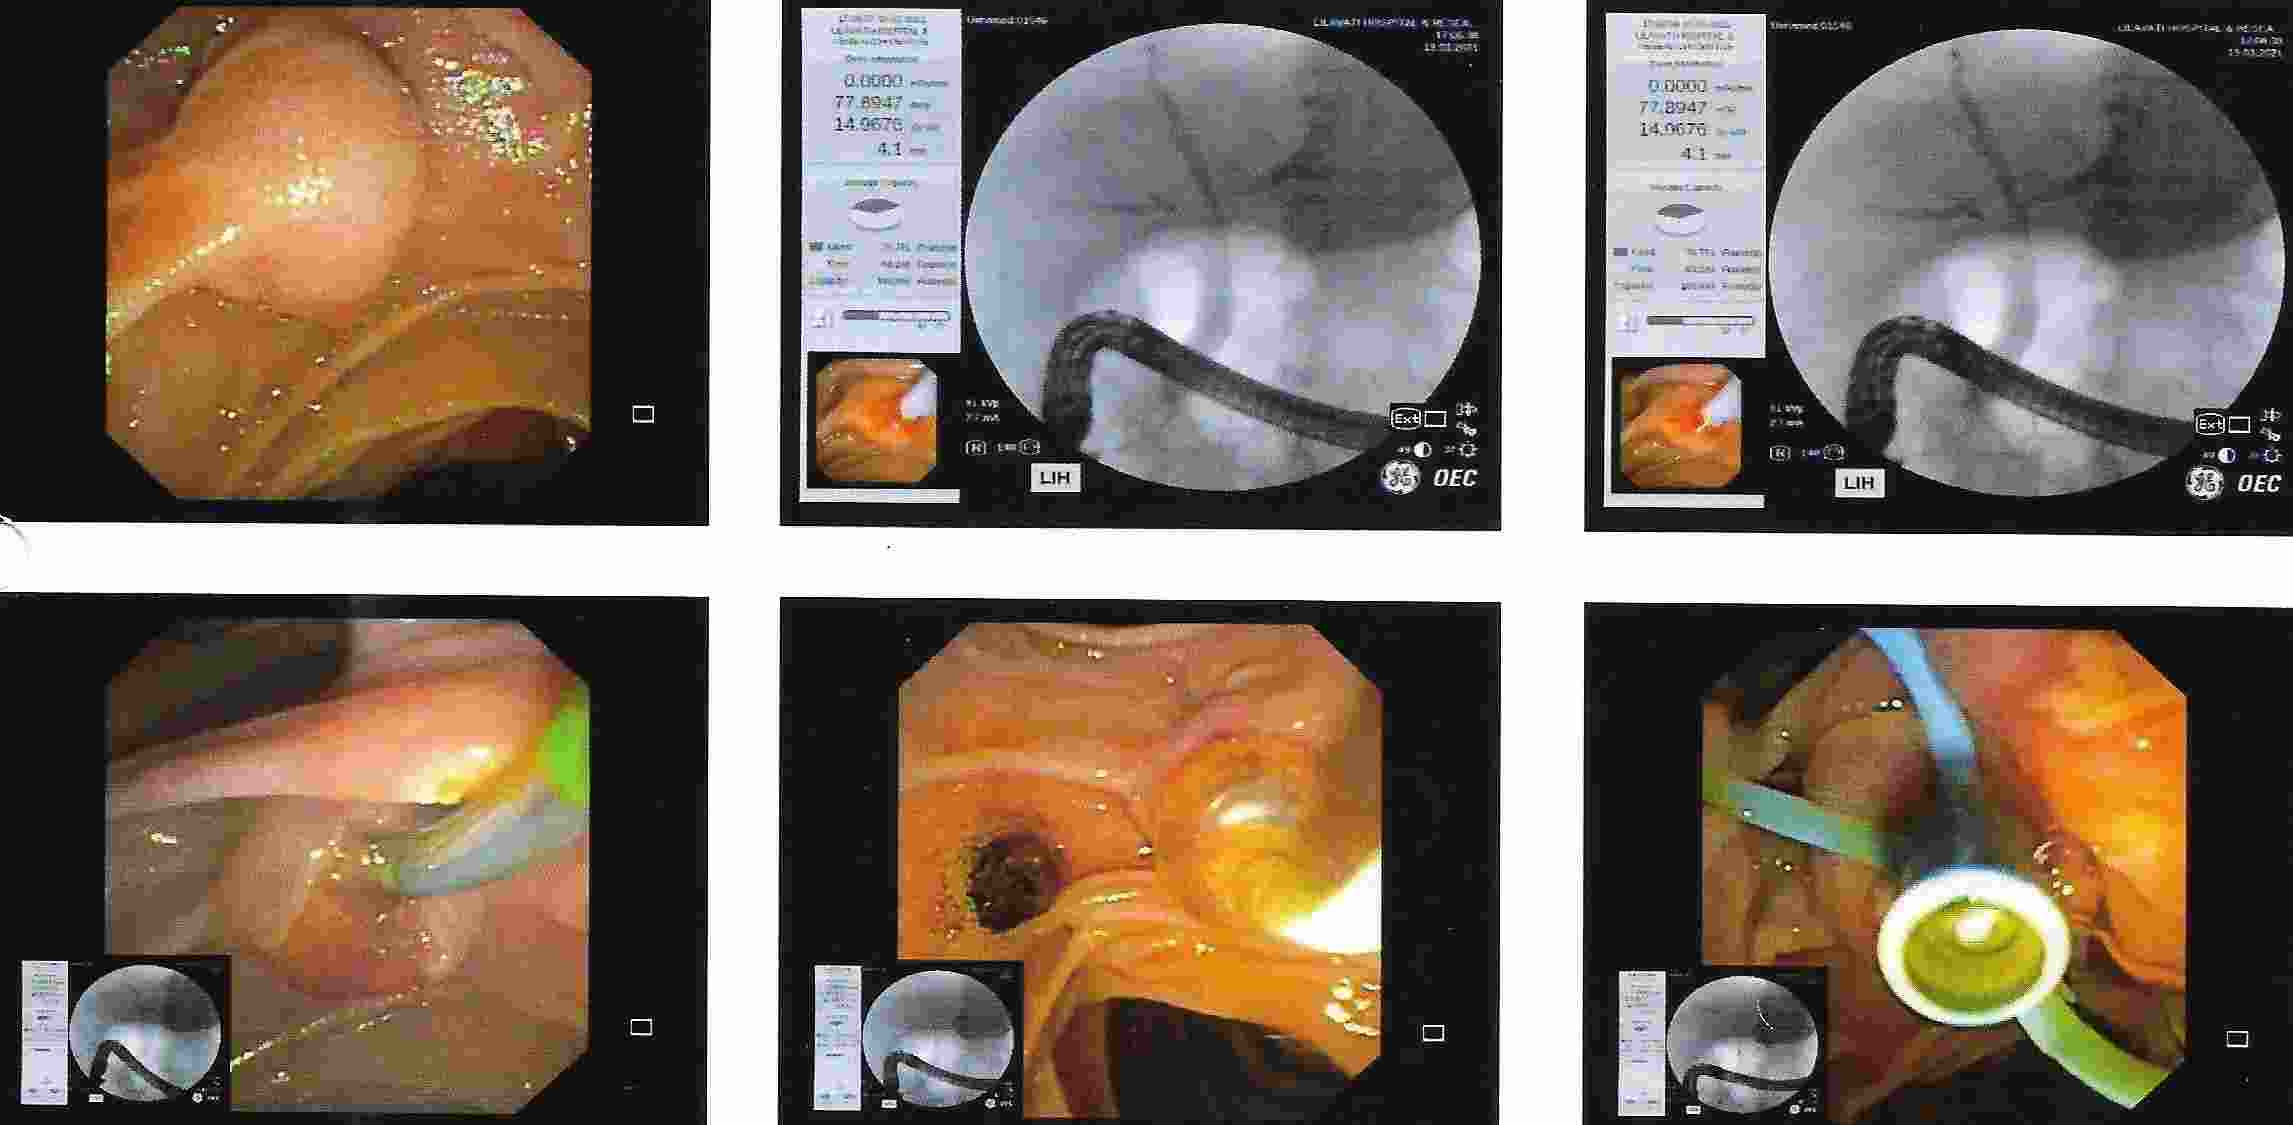

COLONOSCOPY

Colonoscopy is a procedure where the doctor can examine the lowermost part of the digestive tract

by a flexible instrument called as Colonoscope. Common indications for Colonoscopy are

7. Frank blood in the stool, occult blood in the stool or anaemia.

These conditions are seen more often in elderly people where Colonoscopy is essential for making an early diagnosis of cancer of the colon.

Colonoscopy is advocated for first blood relations of the patient who has got cancer of the colon.

Common mistake is to attribute blood in the stool for piles or fissure and get wrongly treated for a long time.

The correct diagnosis of cancer of the colon or rectum if made in time can offer a curative treatment.

Major bleeding in the stool in elderly people is commonly due to diverticulitis of colon.

This is a condition where there are balloon like projections arising from colonic mucosa and

which bleed due to rupture of a blood vessel. Colonic polyps is also an important condition to diagnose because

polyps have potential of becoming cancerous in future. Removal of polyp by polypectomy without

open surgery can offer cure in the early stage of cancer. A proper follow-up can keep the patient free from cancer.

Altered bowel habits, watery or semisolid stools, gripping pain in abdomen, mucus and blood in the stool,

incomplete evacuation can all be due to a condition called as colitis. Colitis has got different causes

like ulcerative colitis, Crohn’s disease, infections, tuberculosis, amoebic colitis, bacillary dysentery and many more.

Corrcet diagnosis by Colonoscopy will allow patients to be treated properly.

IBD - Ulcerative Colitis

IBD - Crohn's Disease

IBD - Small Intenstinal Endoscopy (Enteroscopy)

Cancer of the Colon

Ulcerative Colitis

Ulcerative Colitis

Crohn's Disease

Hemorrhoids

Pain in the rectum or anal region is commonly due to fissure or thrombosed piles and can be

diagnosed by Colonoscopy. Bleeding from colon or narrowing of the colon can be treated by endoscopic

methods without need for surgery.